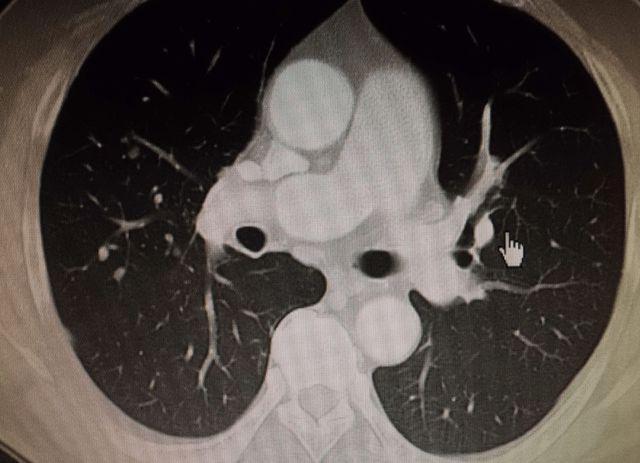

肺ct显示右肺中下叶7mm浅淡结节影,密度不均匀,重建显示为片状病灶